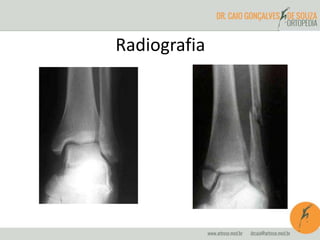

Radiografia